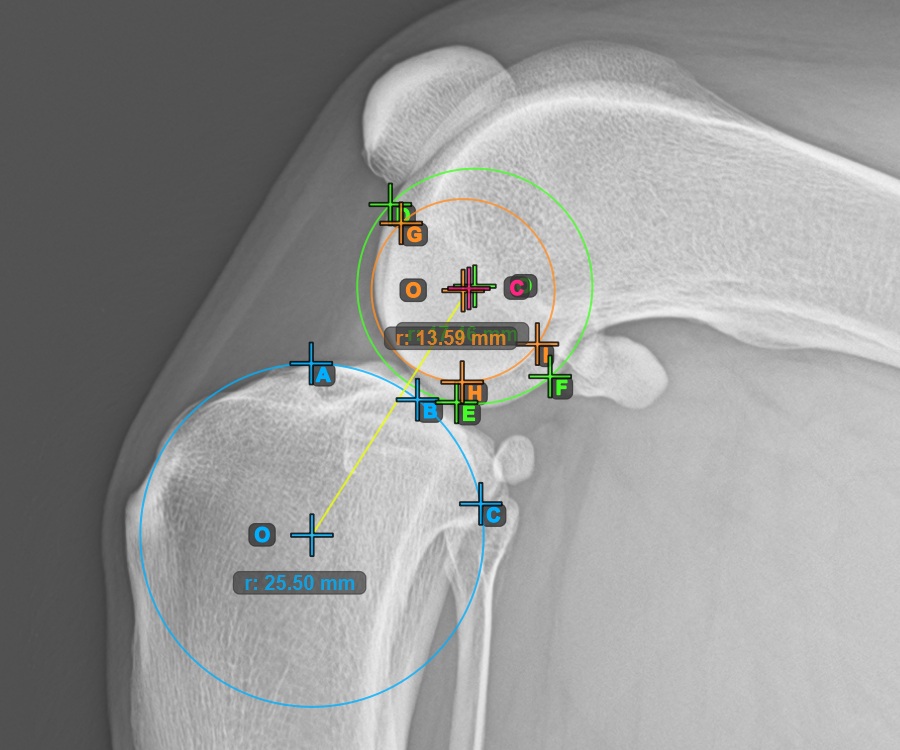

Mark the three points on the inner (secondary) condylus of the femoral bone (Condylus Femoris). Regardless of the order, make sure to mark the most cranial point, the most caudal point and the midpoint of the Condylus Femoris. A circle will be automatically constructed based on the three placed points.

The image below represents a typical placement of the three points on the second Condylus Femoris.